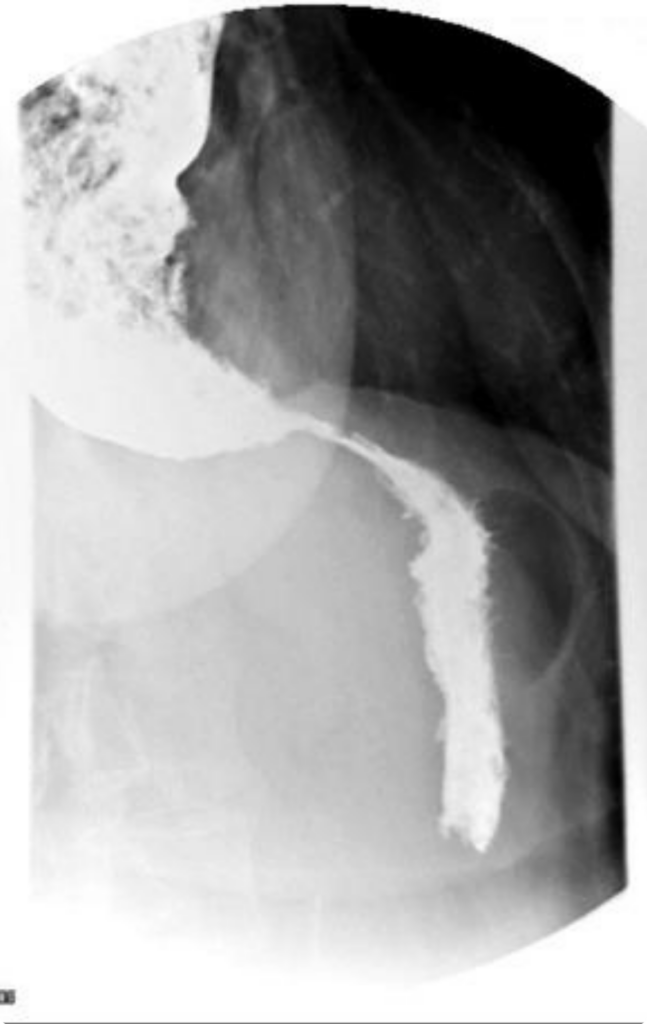

Posteriormente, se realizó un estudio con contraste.

El diagnóstico generalmente se hace mediante manometría esofágica (que mide las contracciones del esófago) y estudios de imagen como radiografías con contraste de bario.